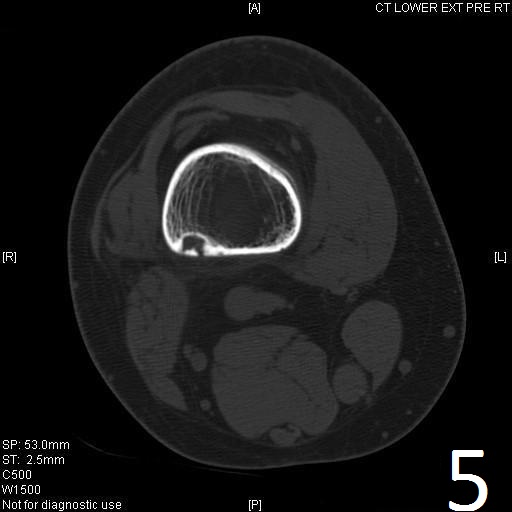

CT

• Useful for determining the true extent of the lesion

• Demonstrates well defined sclerotic borders

• Demonstrates expansile nature and scalloping of bone

• Useful for demonstrating internal trabeculations

Fig. 4-5: Sagittal (Fig. 4) and axial (Fig. 5) CT reconstruction of the lower extremity shows a well circumscribed, small sclerotic cortical lesion consistent with a fibrous cortical defect.